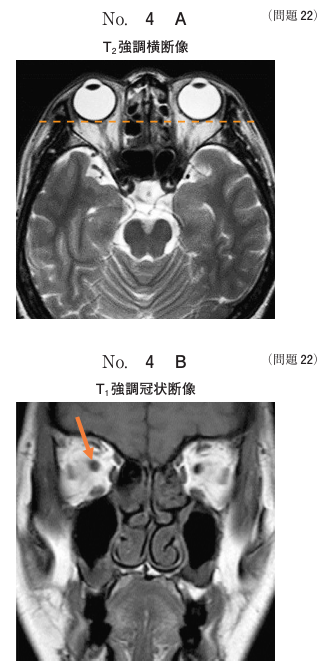

午前/問題22

頭部MRIのT2強調横断像別冊No. 4A と点線のレベルのT1強調冠状断像別冊No. 4B を別に示す。矢印で示す構造はどれか。

1.上直筋

2.下直筋

3.眼動脈

4.視神経

5.動眼神経